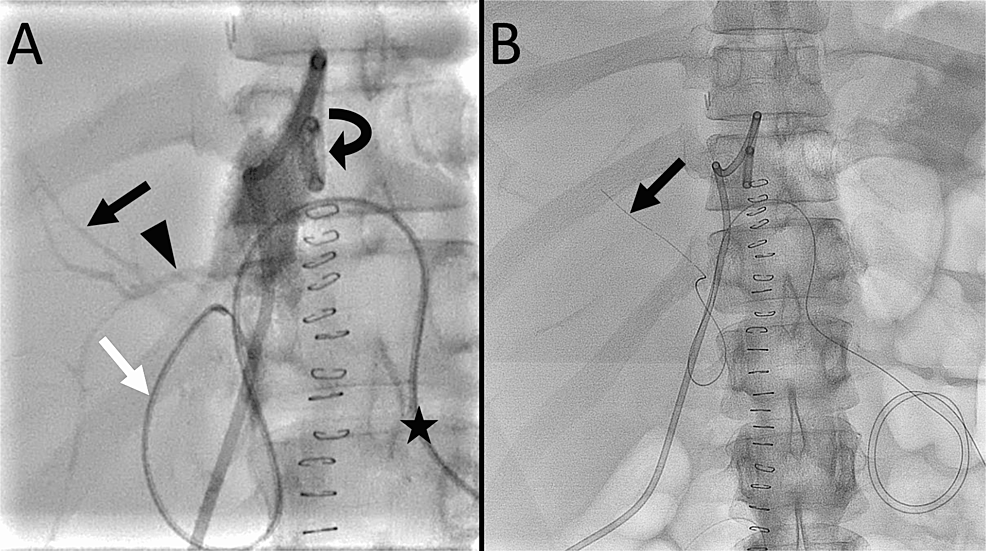

From americanjir.com

Causes and Treatment of Bile Leaks at the Puncture Site After Biliary Drainage Leakage — a bile duct drain, also called biliary drainage, can help treat blocked bile ducts so that bile may flow as it should, helping your liver digest. — various endoscopic treatments (i.e. Biliary stenting, endoscopic biliary sphincterotomy, and nasobiliary. A total of 1028 patients with a median age of 56 years were included. Delayed diagnosis is not uncommon. Biliary Drainage Leakage.

Dual Lumen Microcatheter in Percutaneous Biliary Drainage for Biliary Drainage Leakage Delayed diagnosis is not uncommon due to nonspecific. — a bile duct drain, also called biliary drainage, can help treat blocked bile ducts so that bile may flow as it should, helping your liver digest. — bile leaks can be a complication of abdominal surgeries, specifically trauma to the biliary system. A total of 1028 patients with a. Biliary Drainage Leakage.